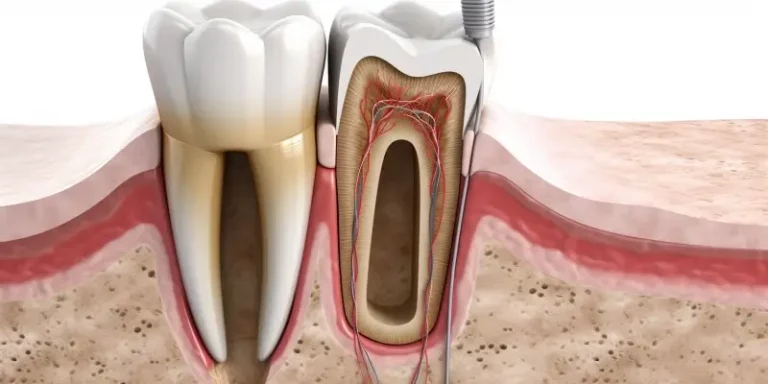

Witamina D odgrywa kluczową rolę w utrzymaniu zdrowia kości i zębów, co jest szczególnie istotne w kontekście zapobiegania chorobom układu…